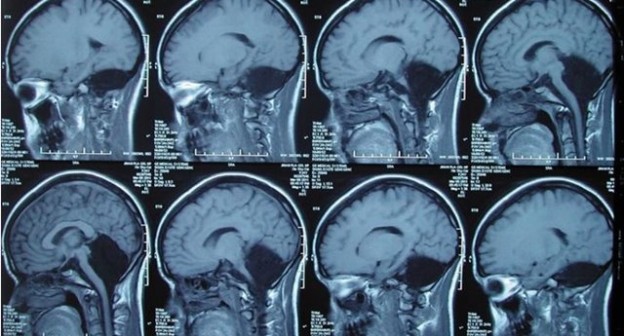

「無腦」「腦袋有洞」,這些罵人吃上官司的話,就字面意義來說真的會發生。中國一名 24 歲的女子在就醫後,醫師非常驚訝地發現,這名女子居然沒有小腦,而原本應該有小腦的部位(上圖大範圍黑色),則填滿了腦脊髓液。

當中國濟南軍區總醫院神經外科副主任張榮偉與功能神經外科中心副主任于鋒醫師等人掃瞄她的腦部,驚訝地發現腦後半部下方原本應該是小腦的部位空無一物,取而代之的是腦脊髓液,他們的報告發表在「腦」(Brain) 期刊。